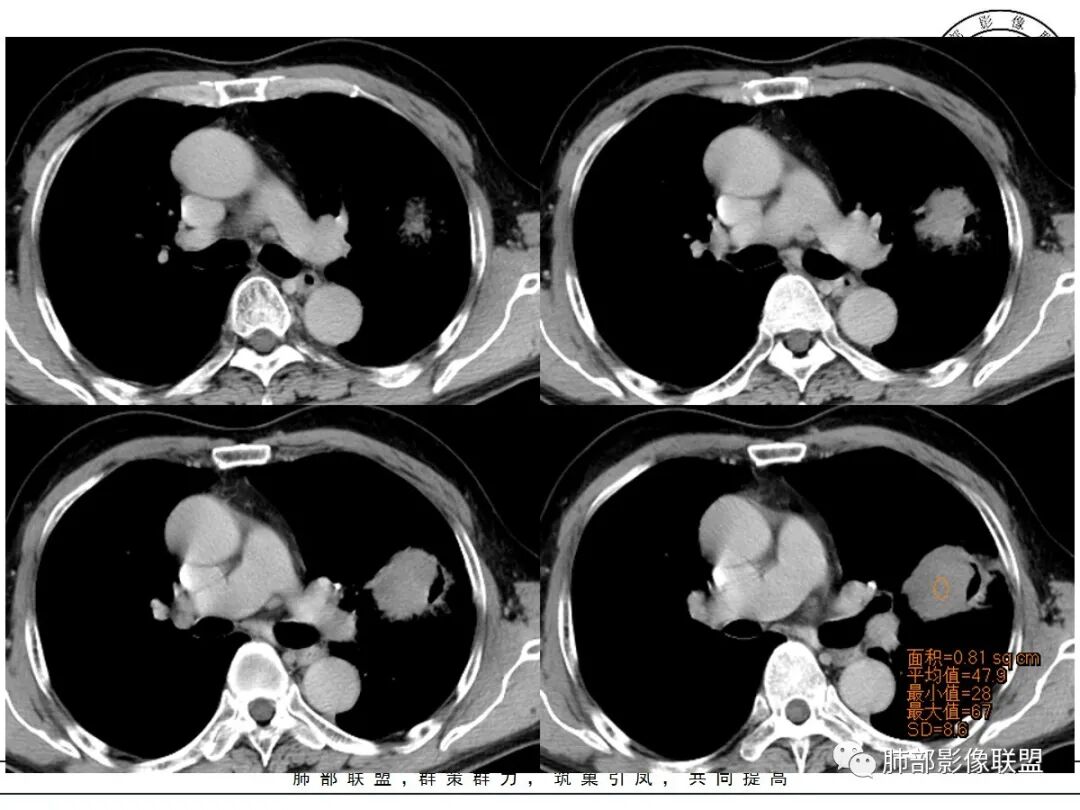

左肺上叶类圆形软组织影,边界较清楚,其内密度均匀,外侧缘可见空气新月征,并可见点状钙化,增强扫描可见均匀强化,病灶周围可见磨玻璃渗出性密度影,斜裂侧光滑平整。考虑炎性病灶,以肉芽肿性炎症为主(如真菌性肉芽肿),鉴别结核(无卫星灶,无多态性),肺癌(无毛刺,分叶等恶性征象,)细菌性炎症(密度一般不这么致密,很少钙化及空气新月征)。

左肺上叶类圆形软组织影,界清,内见空洞影,病灶周围斑片影,可见空气支气管征,未垮叶。考虑炎性病变,糖尿病四大金刚,肺克?毛霉?

老年男性,血糖升高六年,反复咳痰咳嗽3周,左肺上叶近斜裂类圆形肿块影,边缘伴磨玻璃影,边界不清。内部可见支气管走行、钙化、小空洞,叶间裂局部膨隆,增强扫描轻度强化,内部可见小的低密度区,边界尚清。考虑为炎性病变可能性大。

左肺叶裂旁实变影,宽基底与叶裂胸膜相连,边缘平直,部分略膨隆,病灶近段及上段支气管深入病灶内,部分壁略增厚,远端支气管截断,似有小空泡,壁规则,内部可见高密度钙化,周围可见模糊的GGO,血象正常,考虑结核(NTM),鉴别隐球菌,奴卡,放线菌。

老年男性,66,反复咳嗽、咳痰3月。糖尿病,血象不高。

胸部CT:左肺上叶类圆形肿块影,边界较清楚,密度较均匀,内可见小片坏死、偏心空洞、空气新月征、点状钙化,周围晕、絮状渗出、边缘模糊,支气管扩张、充气征、支气管进入病灶堵塞,叶裂牵拉明显,增强扫描中度均匀强化,纵隔可见淋巴结。考虑:炎性病灶,肉芽肿性炎症,曲霉?毛霉?鉴别:TB,淋巴瘤。

左上肺类圆形肿块影,边界较清楚,支气管通畅略扩张,周围磨玻璃影,其内密度均匀,外侧见空气新月征,且见点状钙化。叶间裂光滑稍膨隆。老年男性,糖尿病,高血压,痰培养克雷伯菌。综合考虑炎性病灶,克雷伯合并真菌感染,曲霉。结核合并真菌。鉴别肺癌合并感染。

左肺上叶类圆形软组织影,边界稍模糊,其内密度均匀,外侧缘可见空气新月征,并可见点状钙化,增强扫描渐进性强化,病灶周围可见磨玻璃影,斜裂侧光滑平整,气管未见明显闭塞,淋巴结未见肿大,糖尿病患者,首先考虑感染性变,结核并曲霉?